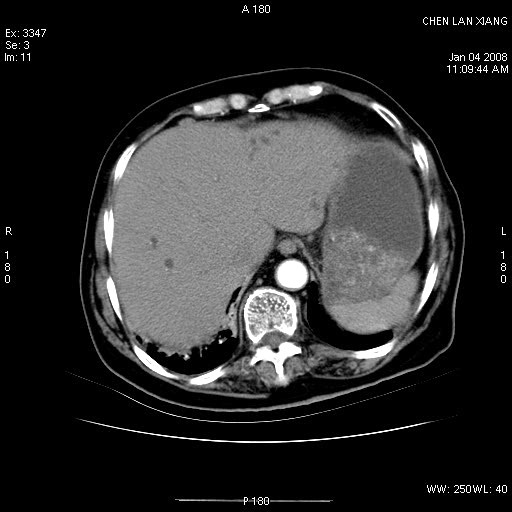

标题: CT11180:女,76岁,腹痛3-4天 [打印本页]

女,76岁,腹痛3-4天,b超示:肝内实性肿物,胆囊强回声,胆总管扩张.

考虑:1、胆总管下端结石伴梗阻性肝内外胆管扩张(肝左叶外侧段肝内胆管多发结石、胆管炎);

2、肿囊癌累及肝,不除外 黄色肉芽肿性胆囊炎。

1 胆总管末端结石伴肝内胆管结石,肝内外胆管扩张。2 胆囊扩大,胆囊壁不规则增厚,内见软组织密度影。考虑:慢性胆囊炎,不除外胆囊癌!

标题: 肝右叶病灶

胆囊癌侵犯肝右叶?

1)胆囊癌伴肝脏转移。2)胆总管下端结石、肝内胆管结石伴肝内外胆管扩张。